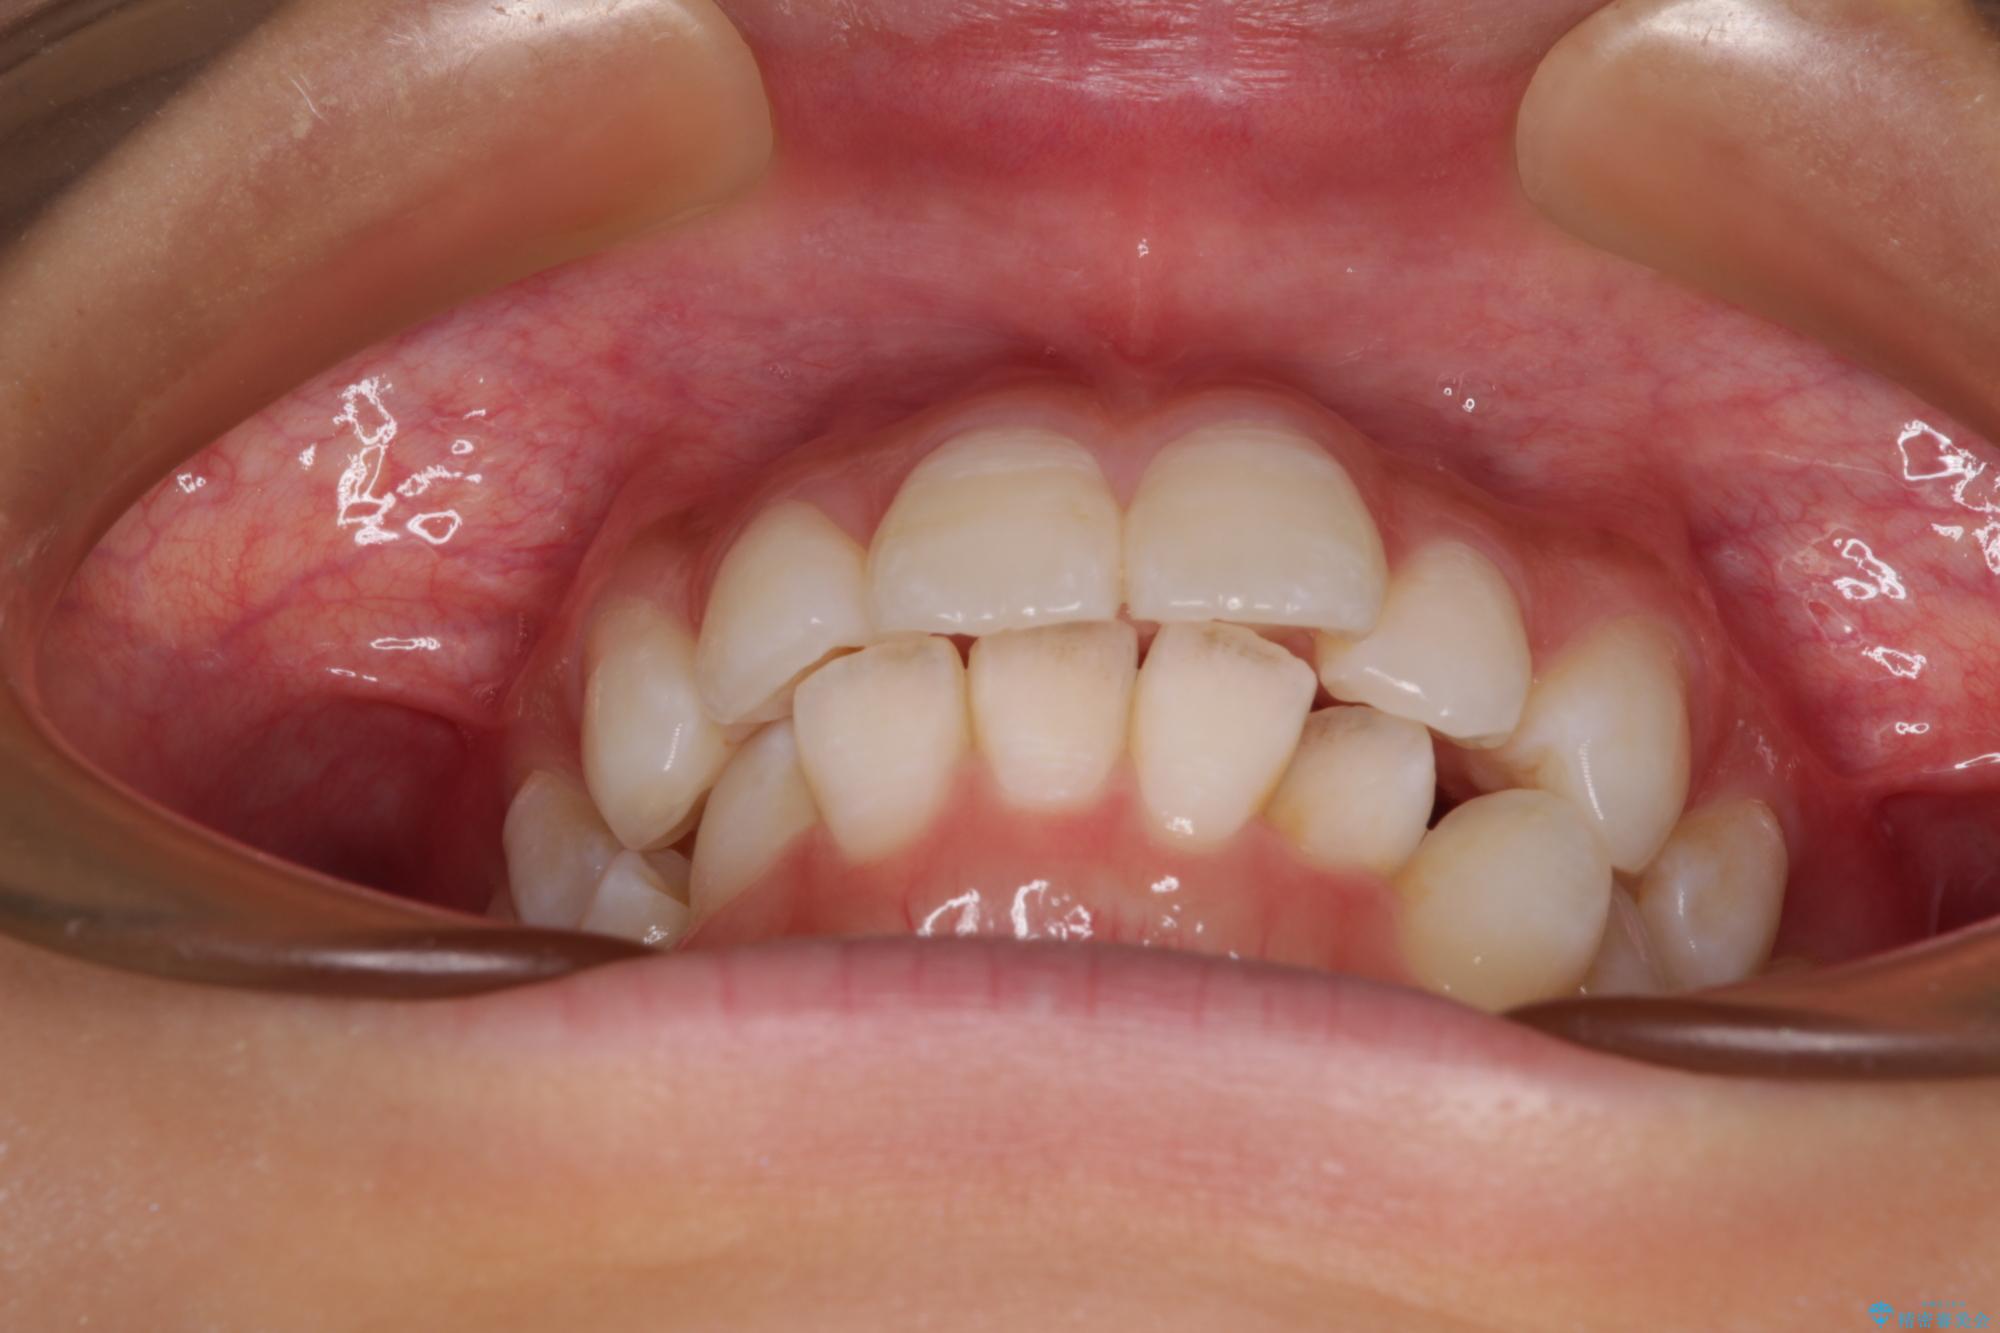

斜め前に飛び出した前歯 抜歯矯正で素敵な横顔に

下唇に前歯が当たって跡が残ってしまう状態でしたが、スッキリとした口元に仕上げることができました。

- 口を閉じたときに飛び出してしまう上顎前歯を気にして来院された患者様です。